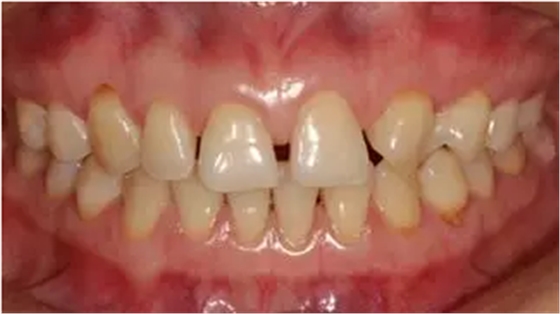

術(shù)前微笑照

術(shù)前全牙弓咬合照

術(shù)前全牙弓非咬合照

口腔衛(wèi)生尚可,牙齦正常。11,12,21,23 牙體完整,散在間隙,13、24、33、34 頸部楔形缺損,探診無明顯不適,叩(-),無明顯松動(dòng)。冷熱刺激無明顯不適。22 缺失。上下牙咬合穩(wěn)定,覆 覆蓋正常。